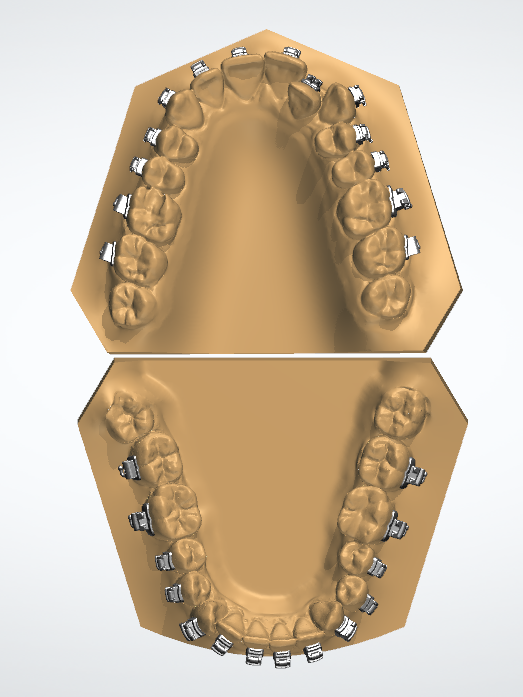

Полный расчет исходной ситуации в 3D цефалометрии. Составление плана лечения (ортосетап) в программе 3D Shape Ortodont.Загрузка КТ пациента-учет «движения корней» при лечении. Единственно правильный перенос положения брекетов или элайнеров - 3D печать полученного в программе результата (примеры представлены ниже на фото).

Наличие программного обеспечения позволяет использовать цифровые данные, полученные при диагностике в изготовлении протезов, шин, коронок без проблем «человеческого фактора», что очень важно при заболеваниях ВНЧС.